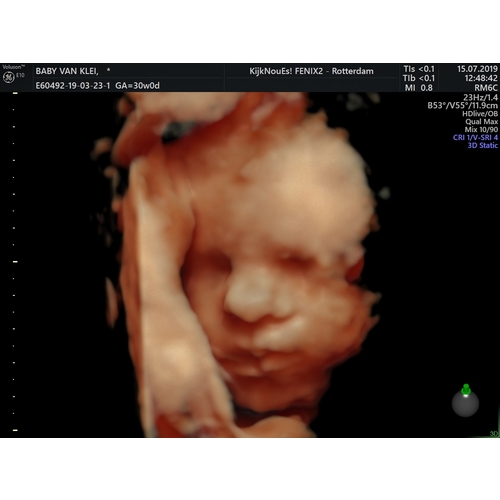

Staan ze er vanavond ook ? En wat kost het als ik vragen mag ? Wij hebben deze met 28 weken een 3D echo laten maken..zoooo speciaal. Bijna verslavend, dus zou het zo weer willen doen. Al denk ik dat het voor mij te laat is. 33weken, zal lastig worden om haar goed in beeld te krijge

Ze staan er volgens mij elke dag! Kost 50 euro krijg je twee foto's geprint en een USB stick met alle foto's. ( Het is trouwens ook allemaal voor je goede doel ) Ik vond het echt leuk en de moeite waard ook al zie je nog niet hoe de baby er verder precies uitziet. Juist een toffe ervaring en doe het met 28 weken gewoon weer